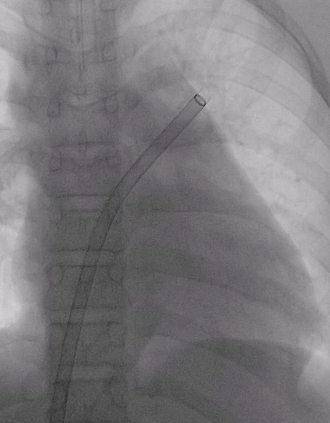

展开左右盘面

左盘展开

右盘展开并造影

基本无残余分流